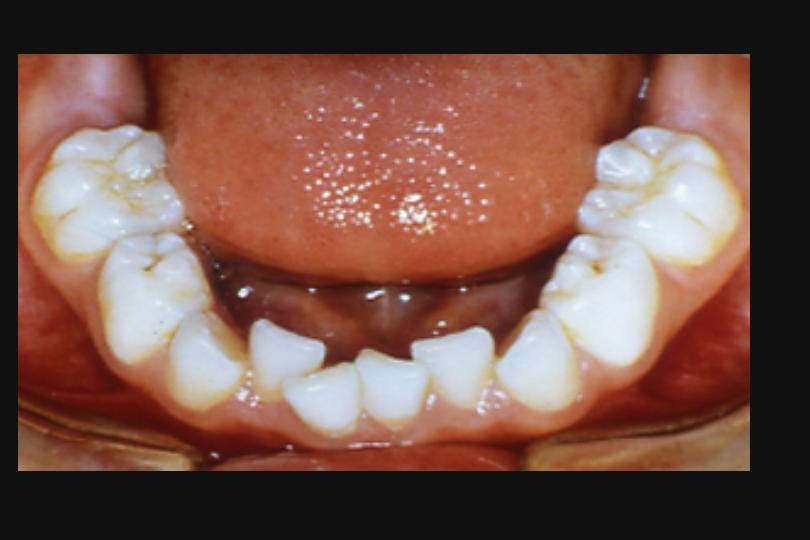

何故なら、下顎の乳前歯はもっとも早く生えるため、スペースは十分なはずだ。(図4)

図4

図4:下顎の乳前歯は、スペースがあるのにどうして叢生になるのだろう?